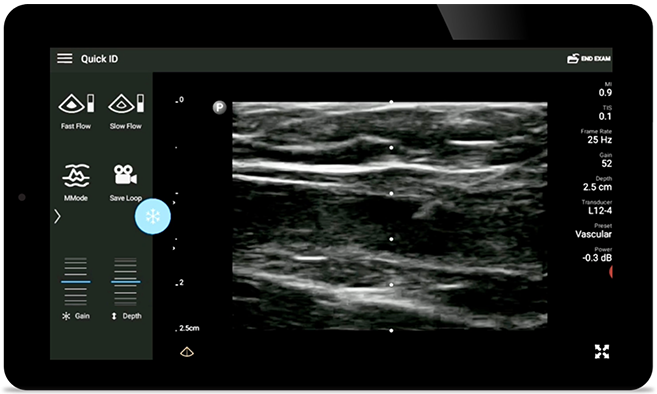

Disminuya las complicaciones de las inserciones de CVC

La guía por ultrasonido en tiempo real puede mejorar la precisión y la seguridad de las inserciones de CVC.

Transductores Lumify para medicina interna

Transductor de matriz lineal de banda ancha Lumify L12-4

• Rango extendido de frecuencias de operación entre 12 y 4 MHz • Tamaño de apertura: 34 mm • 2D, Doppler orientable a color, Modalidad M, XRES avanzado e imágenes armónicas multivariables, SonoCT • Imágenes de alta resolución para aplicaciones superficiales: tejidos blandos, vasculares, superficiales, musculoesqueléticos y pulmonares • Marcador de línea central • Transductor USB-C con cable reemplazable